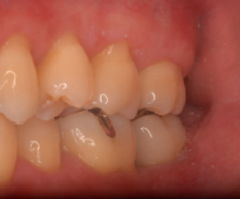

歯周病が進行し、グラグラして物が嚙めず、抜歯してインプラントにしていくことに。

インプラントはストローマンを使用、上部構造はジルコニアセラミックス